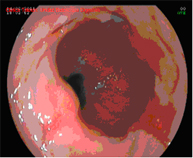

Técnica 1Técnica 1 Técnica 2Técnica 2

Técnicas Endoscópicas de Tratamiento del Esófago de Barret

Mucosectomía endoscópica

La mucosectomía consiste en la resección por vía endoscópica de una sección de la mucosa y submucosa (en este caso esofágica). Esta indicada siempre que en la endoscopia diagnóstica se aprecien lesiones sobreelevadas en el esófago de Barrett.